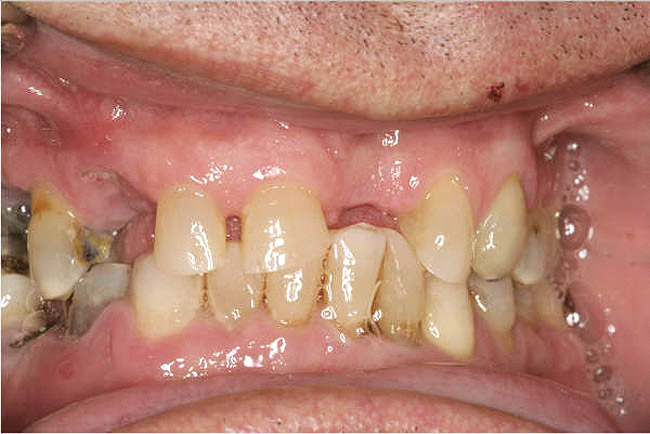

Diminished Crown Height Space

Diminished crown height space has several different solutions which depend on the patient’s anatomical limitations as well as his or her perceived needs. If the problem is the opposing arch, the solution may be fixed prosthodontics to level the occlusal plane (Figure 10A through Figure 10D). It may be intrusion of teeth with orthodontics or some combination of the two. If there is too little crown height space and the patient is edentulous, the solution may be to increase the vertical dimension of occlusion (VDO) with a removable prosthesis.17 If the patient has a partial dentition, it may involve traditional fixed prosthodontics to alter the VDO.18 The patient may need a surgical approach, such as an osteoplasty, before implant placement (Figure 11A and Figure 11B). However, without an initial diagnosis, there is no way of formulating a solution to an unknown problem.

Figure 10a  Supra-eruption of the opposing arch, thus diminishing crown height space.

Figure 10a

Figure 10b  Supra-eruption of the opposing arch, thus diminishing crown height space.

Figure 10b